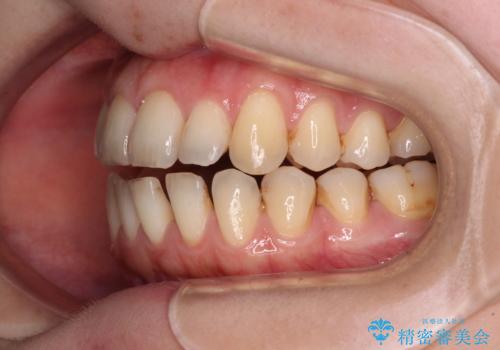

- 上下前歯の隙間を気にして来院された患者様です。

下顎前歯が1本欠損しており、上下小臼歯はクロスバイトとなり、上下前歯の接触もないという不正咬合の状態でした。

クロスバイトはワイヤー矯正が得意とするところであり、上下前歯の非接触や開咬はインビザラインの得意とするところであるので、ワイヤー装置により事前にクロスバイトを改善し、その後にインビザラインにて仕上げていくこととしました。